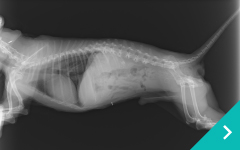

低侵襲尿管・尿道・膀胱結石治療

低侵襲

尿管・尿道・膀胱結石治療